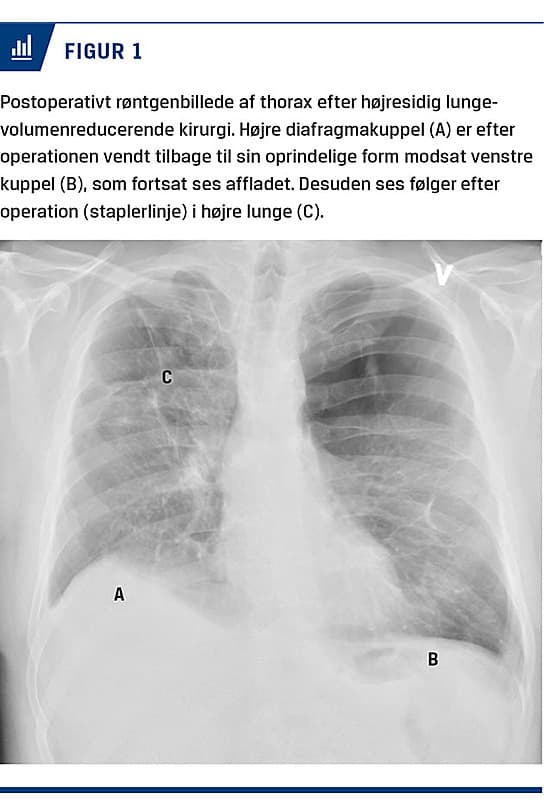

Emfysem er en hyppig kronisk lungesygdom, der medfører et progredierende tab af de elastiske fibre i lungen. Dette fører til øget komplians, som fører til, at lungerne ekspanderer ved inspiration og får sværere ved at tømme sig igen ved eksspiration, hvilket skaber hyperinflation, som igen forårsager strukturelle forandringer af brystvæggen og affladning af diafragma (Figur 1). Konsekvensen er luftvejsobstruktion og åndenød ved fysisk aktivitet.